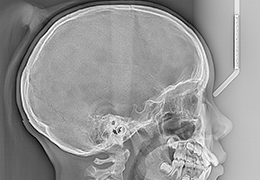

View X-Ray CT & MRI Scans Fast and Easily

Designed for surgeons, Pro Surgical 3D makes it easy to view patient scans quickly. Pro Surgical 3D facilitates the optimal 3D treatment and assessment workflows based on X-ray CT and MRI scans – and best of all, it’s FREE!

Traditional multi-planar slicing

Multi-planar slicing.

Oblique slicing.